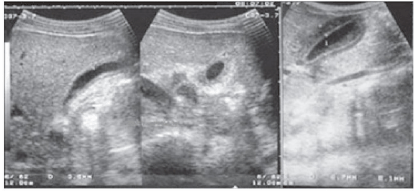

A febre do dengue hemorrágico (FDH) é uma arbovirose responsável por epidemias anuais no Brasil. Sua principal característica é o aumento da permeabilidade capilar, representada pela fuga de líquido e albumina para o espaço extravascular, levando a derrames cavitários e hemoconcentração com elevação do hematócrito, descrita como polisserosite, classificada em formas leves e graves, segundo critérios da Organização Mundial da Saúde. Embora os achados à ultrassonografia sejam inespecíficos, o método contribui para o diagnóstico precoce em pacientes com FHD e no diagnóstico diferencial de outras doenças febris.

Considerando as informações abaixo, assinale a alternativa correta quanto a principal hipótese diagnóstica da imagem ultrassonográfica apresentada.